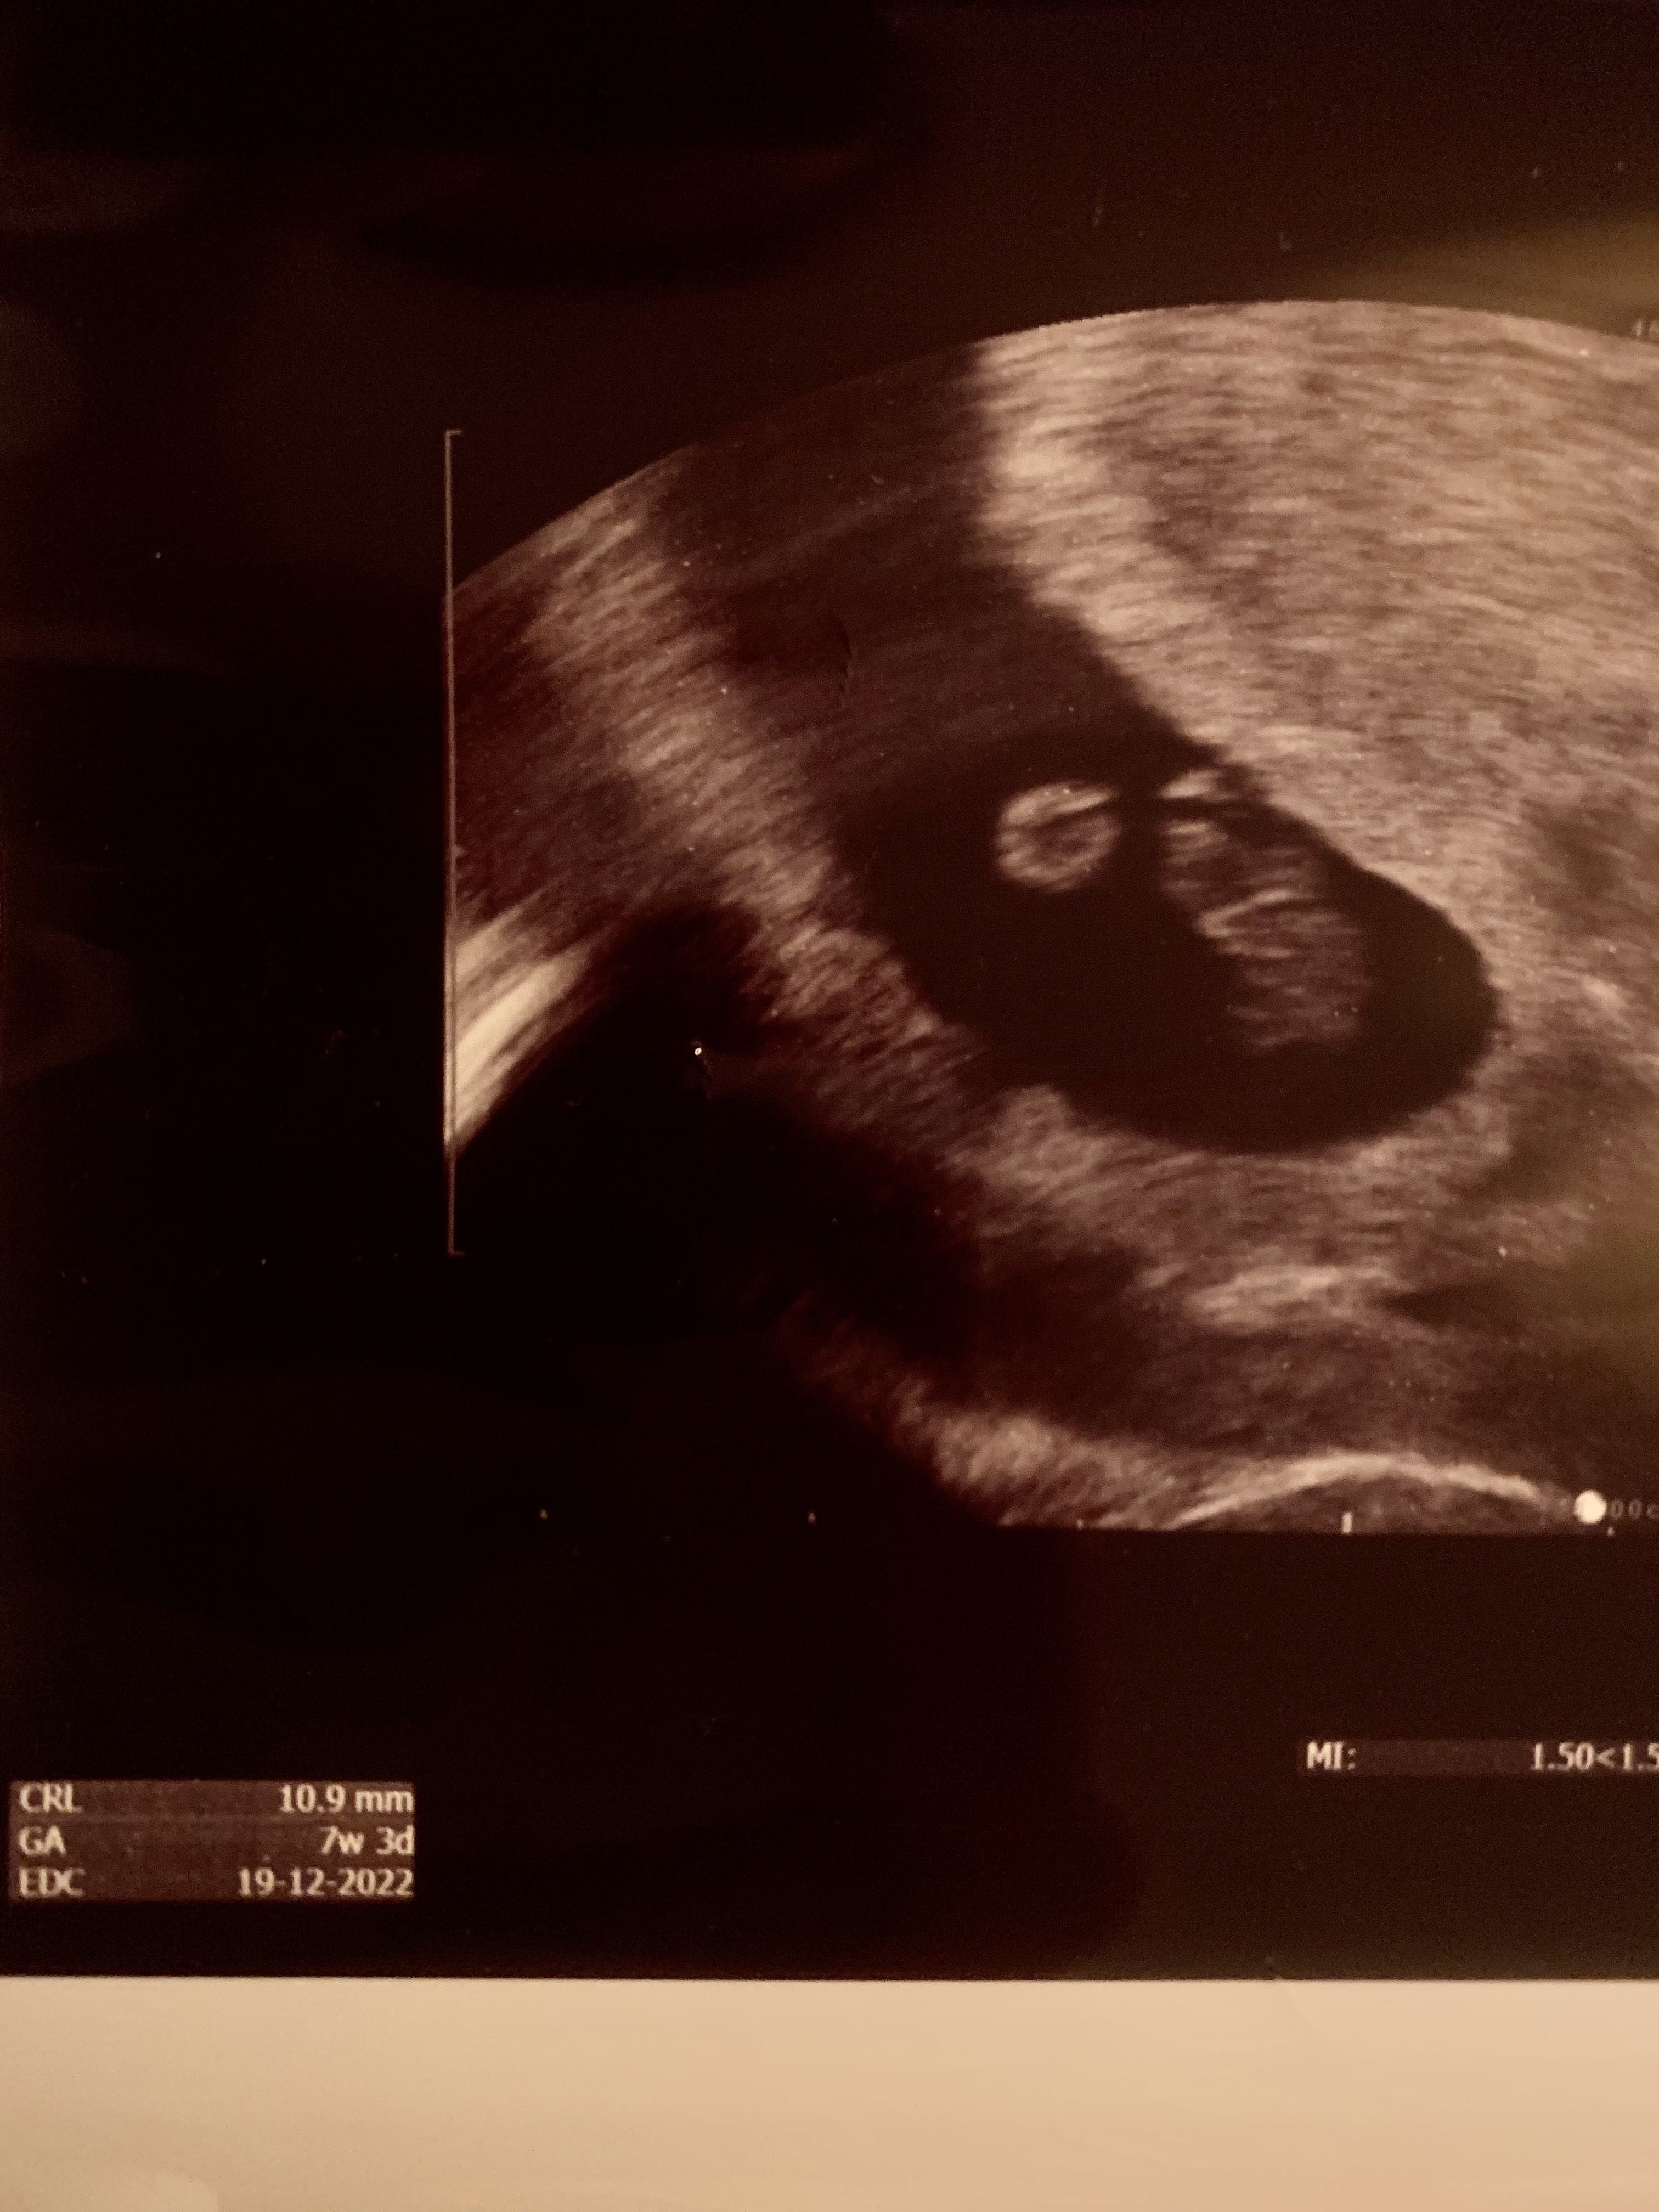

Ja już po pierwszym usg. 7+3 dokładnie, tak jak w apce :) Wg ginekog rozmiar prawidłowy i serduszko bije idealnie. Ale jestem szczęśliwa 😍